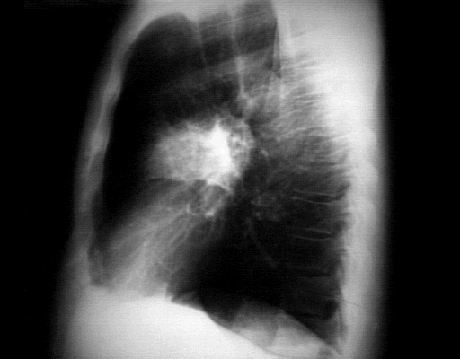

Lateral

In this lateral view, the radiodensity or infiltrate is superimposed on the hilar area and can be localized to the anterior segment of the right upper lobe.